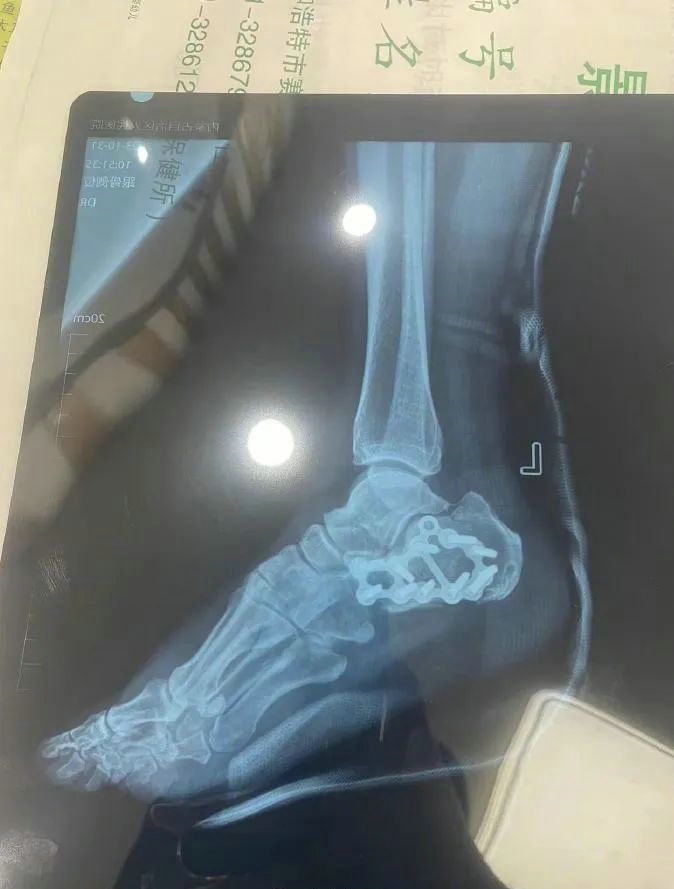

“那時候我剛工作了兩天,在第三天10月22日下午施工過程中從三層高的鐵架上摔了下來,導致30厘米左右的鋼筋刺穿我的右側(cè)臀部,左腳跟也粉碎性骨折,被送往內(nèi)蒙古自治區(qū)人民醫(yī)院救治,當晚做了手術取出刺在右臀部的鋼筋,10月30日又進行了左腳粉碎性骨折手術?!崩紫壬嬖V記者。